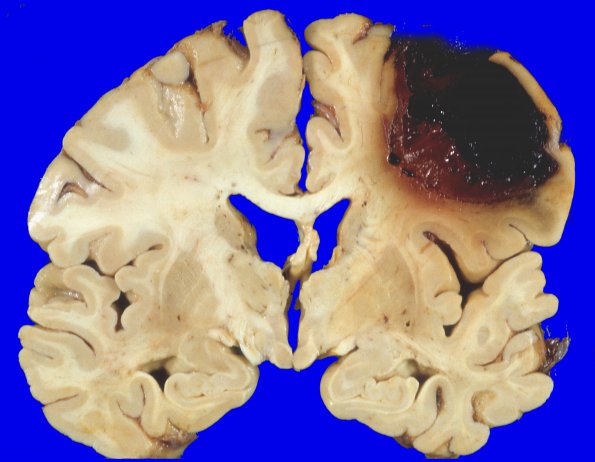

23A1,2 A large lobar hemorrhage at two coronal levels.